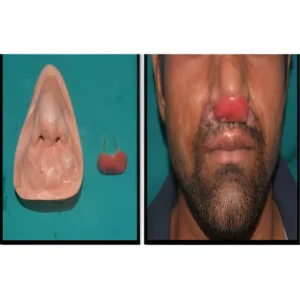

Types of Extra-Oral Prosthesis

Nasal Prosthesis

A prosthesis that is specifically designed to restore the aesthetic form and anatomic contours of a nose that has been partially or completely lost due to trauma, congenital malformation, or surgical resection (e.g., due to cancer).